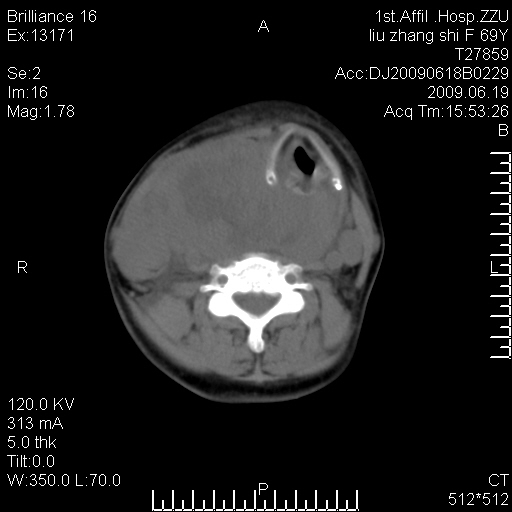

标题: CT26782:女,69岁,颈部占位,3天后公布病理结果。

【病理证实系列】女,69岁,颈部占位,有病理结果,3天后公布。(由于病例时间较久,临床资料不全,请网友见谅)本系列将有几百种常见、少见及罕见病例,均经病理证实。病例资料来自郑州大学第一附属医院。与网友共享,本人有空就发。

甲状腺癌并颈部淋巴结转移。感谢楼主的良苦用心,谢谢。

甲状腺癌并颈部淋巴结转移。

需与鼻咽癌鉴别!

支持甲状腺癌广泛侵及周围结构并颈部淋巴结转移。

鉴别:淋巴瘤、恶性神经源性病变、恶性纤维组织细胞瘤。

病理结果:颈部非霍奇金淋巴瘤。

右侧甲状腺确实有问题